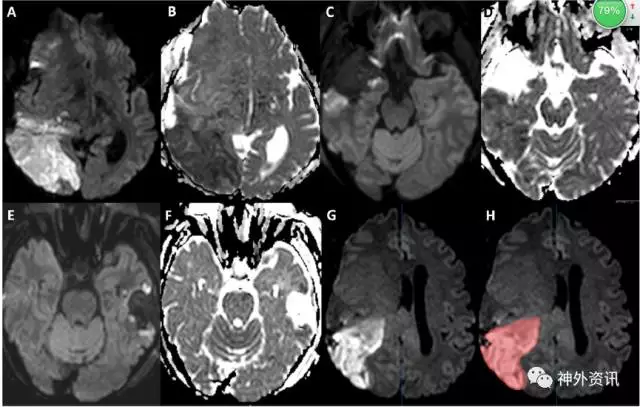

结果显示,179例患者共行201次手术。其中,159例的术后MRI成像显示缺血性脑梗死,脑梗死体积0.5–6.7cm3,平均为2.1cm3(图1)。计算所有参数的spearman相关系数后,发现术中平均舒张压(dBP)(rho -0.239;95% CI -0.11--0.367,p=0.017)、液体平衡状况(rho 0.236;95% CI 0.1-0.373;p=0.017)和术中平均动脉压(MAP)(rho -0.206;95% CI -0.07--0.34;p=0.041)与脑梗死体积呈相关性。采用等级回归模型,排除年龄和复发肿瘤等的混杂因素后,显示术中平均舒张压、液体平衡以及手术的时长是脑梗死体积的独立风险因子。单变量生存分析提示,术中平均舒张压、平均动脉压以及手术时长是脑梗死预后的预测因子。多变量模型表明,手术时长仍为患者预后的预测因子(HR=1.003;95% CI 1.000-1.007;p=0.027)。

图1. 脑肿瘤切除术后患者的MRI成像显示脑梗死体积。